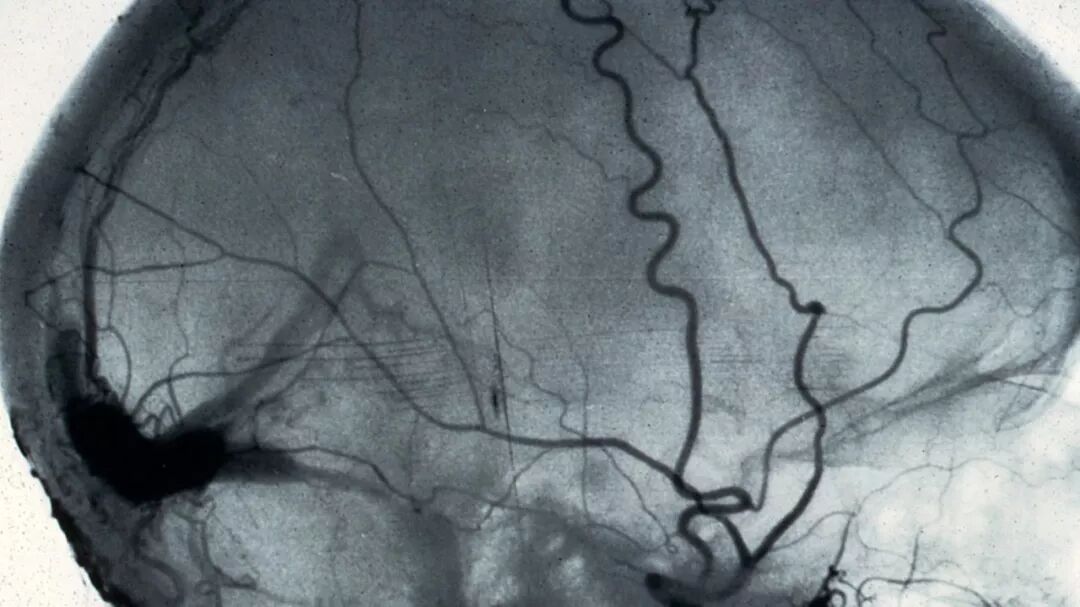

△ 血管造影术(angiogram)拍到的脑部血管。 血管造影术是利用X光观察血管堵塞的医学方法。